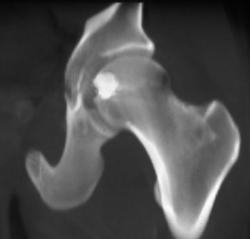

Right Femur Fracture